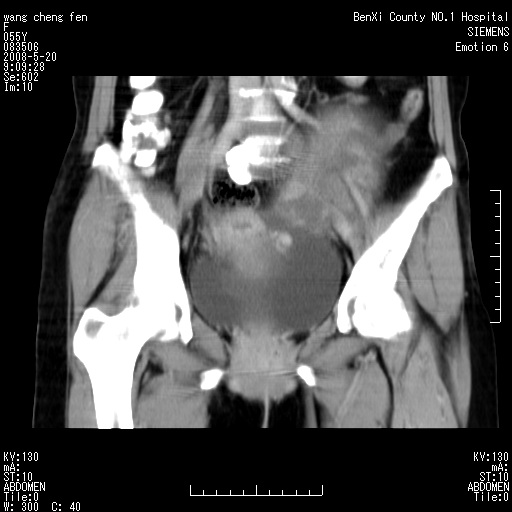

女、绝经后阴道流血3个月

左侧附件区可见一囊性占位,边缘清楚,内可见不规则形软组织影 ce:囊壁及内部可见强化 考虑 卵巢囊腺瘤

左侧附件区巨大囊实性病灶,边缘光整,病灶囊壁较厚,增强示囊壁及实性部分明显强化,强化呈度与宫体实质大致相同,宫腔积液征像,未见盆腔积液等其他异常,考虑左侧卵巢囊腺癌,不除外囊腺瘤及浆膜下肌瘤坏死

左侧附件区巨大囊实性病灶,边缘光整,病灶囊壁较厚,增强示囊壁及实性部分明显强化,强化呈度与宫体实质大致相同,宫腔积液征像,未见盆腔积液等其他异常。绝经后阴道流血3个月,结合病史左侧卵巢囊腺癌首先考虑,宫腔扩大不除外累及。期待结果。